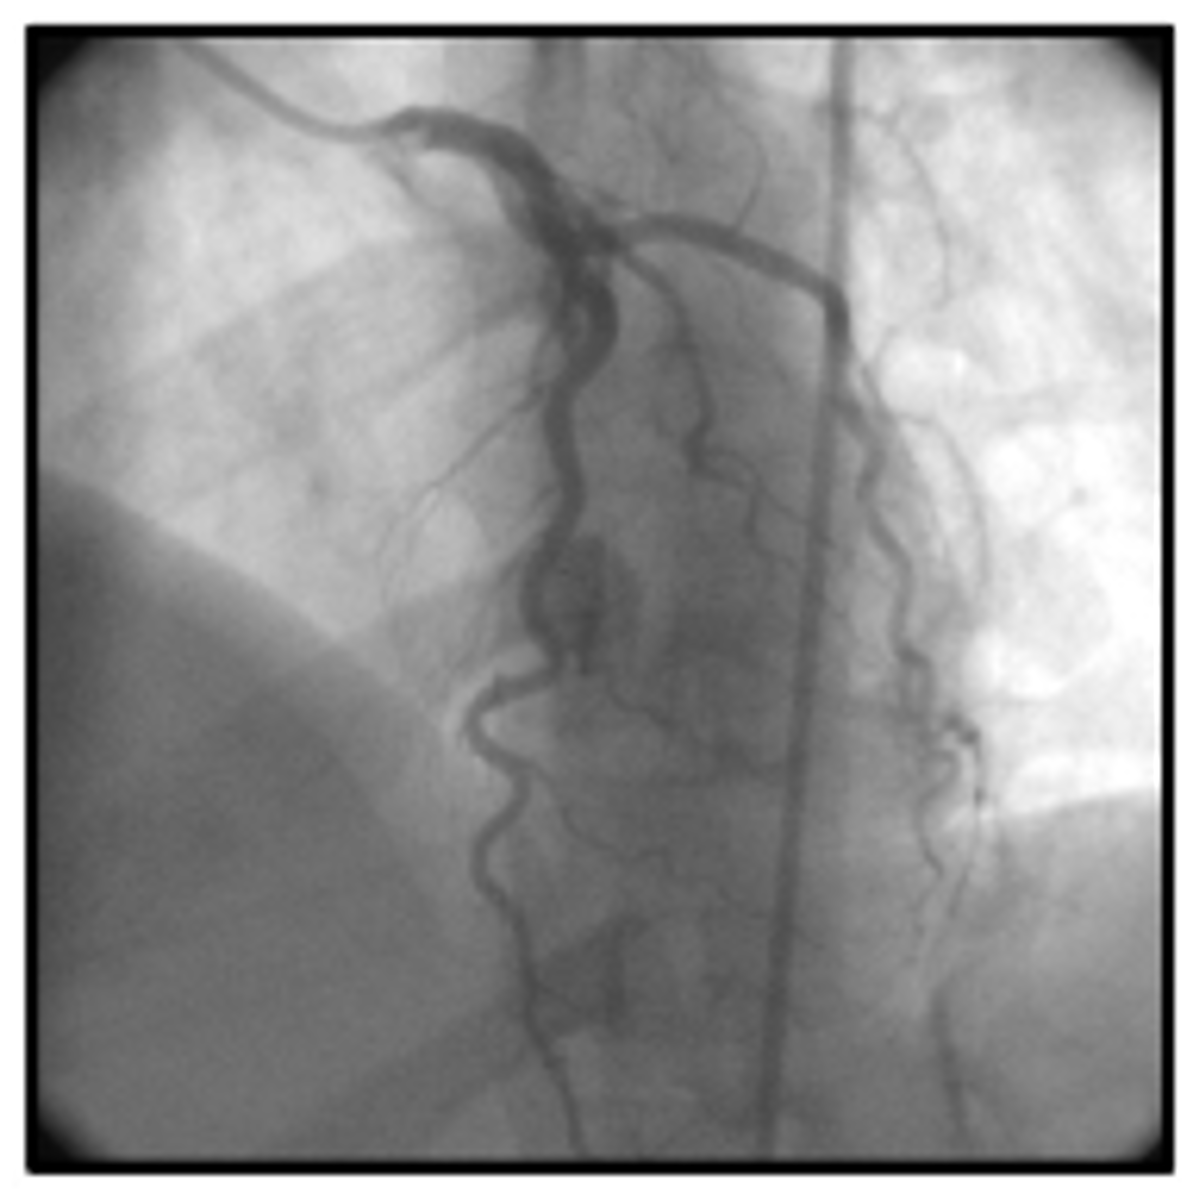

myocardial bridge

a segment of the LAD that occludes during systole and opens during diastole